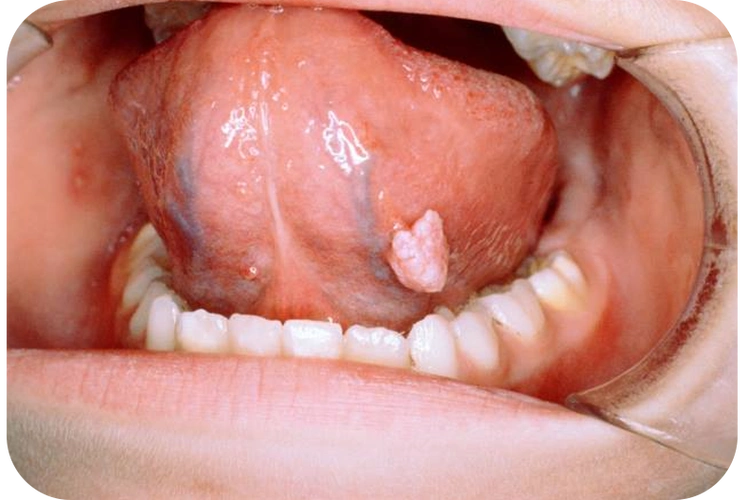

正常人口腔很难长尖锐湿疣-张磊-爱问医生